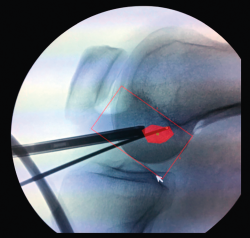

La posición del túnel femoral ha sido la que más cambios ha experimentado en las últimas décadas. Las primeras plastias con técnica monotúnel (con un túnel femoral prácticamente vertical) ofrecían muy buena estabilidad anteroposterior, pero con escaso control de la estabilidad rotacional y frecuentemente con un pivot shift test positivo en el postoperatorio. Las nuevas técnicas tienden a horizontalizar la plastia a través de un portal accesorio anteromedial (Figuras 11A y 11B), dando así mayor estabilidad dual, tanto anteroposterior como rotacional. Este gesto técnico, con la rodilla en posición artroscópica de flexión, puede provocar un túnel femoral excesivamente anterior, con la consecuente pérdida de función estabilizadora de la plastia. Es muy importante hallar la huella anatómica del LCA original. El cambio de portal artroscópico para su correcta visualización es un gesto técnico sencillo y de utilidad (Figura 12).

Figura 12. Visión artroscópica desde el portal anteromedial.